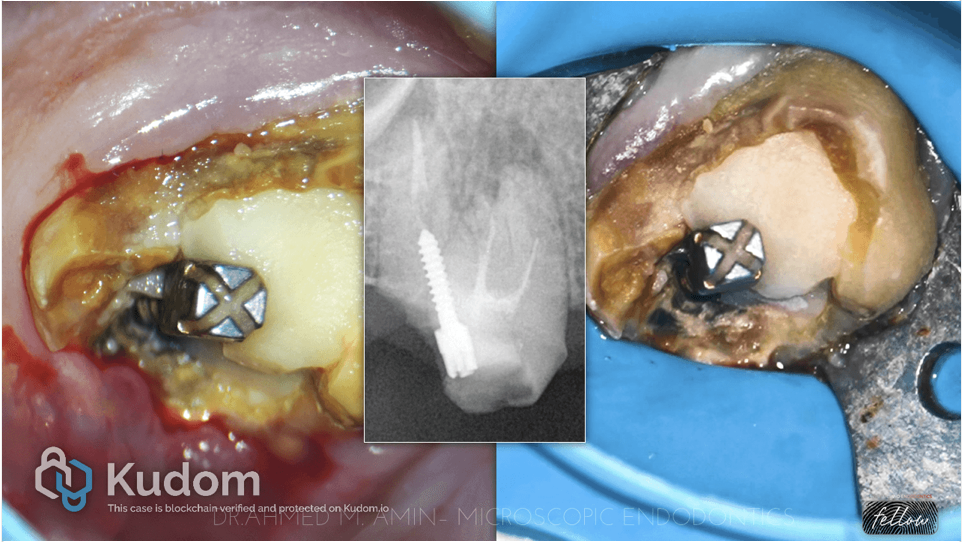

Fig. 3

1st & 2nd XRAY : Here, we removed the metal post using ultrasonics, and then we removed all the gutta-percha.

scout the canals and bypassd the ledge

Taking working length

Catching the MB2 canal

Preparation for all canals

3rd Xray : Intracanal medication to elevate the PH and to act as antibacterial

4th XRAY : Master cone fitting xray

5th XRAY : Obturation of Mesials & DB Canal with WVC + Bio C Sealer

Then we decided to obturate the palatal canal with MTA apical plug.

“X-ray of plugger fit 2 mm short of the working length”